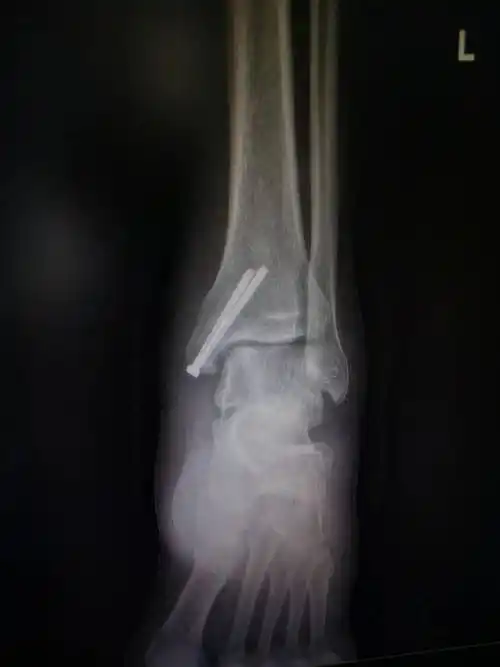

脚崴了,要拍个片吗?_韧带_小方_受伤